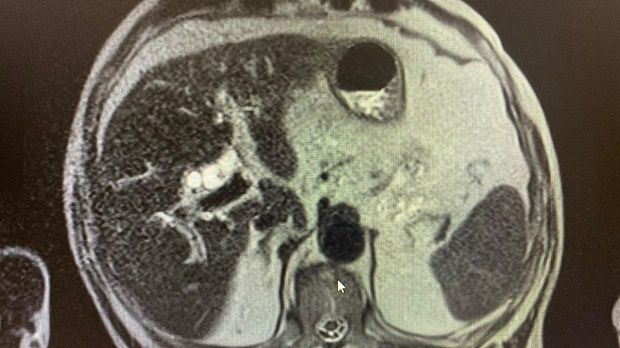

2)Биохимический анализ крови: Билирубин- 82,4 , прямой- 47,5 АЛТ- 92 , АСТ-136 , С-реактивный белок -44,4 скорость клубочковой фильтрации- 45 . МРТ: внутри- и внепеченочные протоки расширены , общий печеночный проток до 18 мм, холедох до 14 мм, в просвете конкременты до 14 мм. Заключение: Холедохолитиаз . Билиарная гипертензия.

На следующий день произведена ретроградная холангиопанкреатография.

Отмечатся юкстапапиллярное расположение большого дуоденального сосочка тип-3. Канюляция папиллотомом pull-type ,контрастирование водорастворимым контрастом .

Рентгенологическая картина расширенния желчных протоков и наличие конкрментов в холедохе. Произведена эндоскопическая ограниченная папиллосфинктеротомия, отмечалось поступление темной желчи. Ревизия корзиной Дормия дали основания полагать ,что конкременты плотной консистенции.